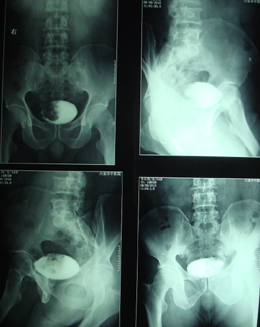

典型病例,男,56岁。无痛性血尿3月。

膀胱占位性病变,呈菜花状生长,考虑膀胱癌。 期待病理。